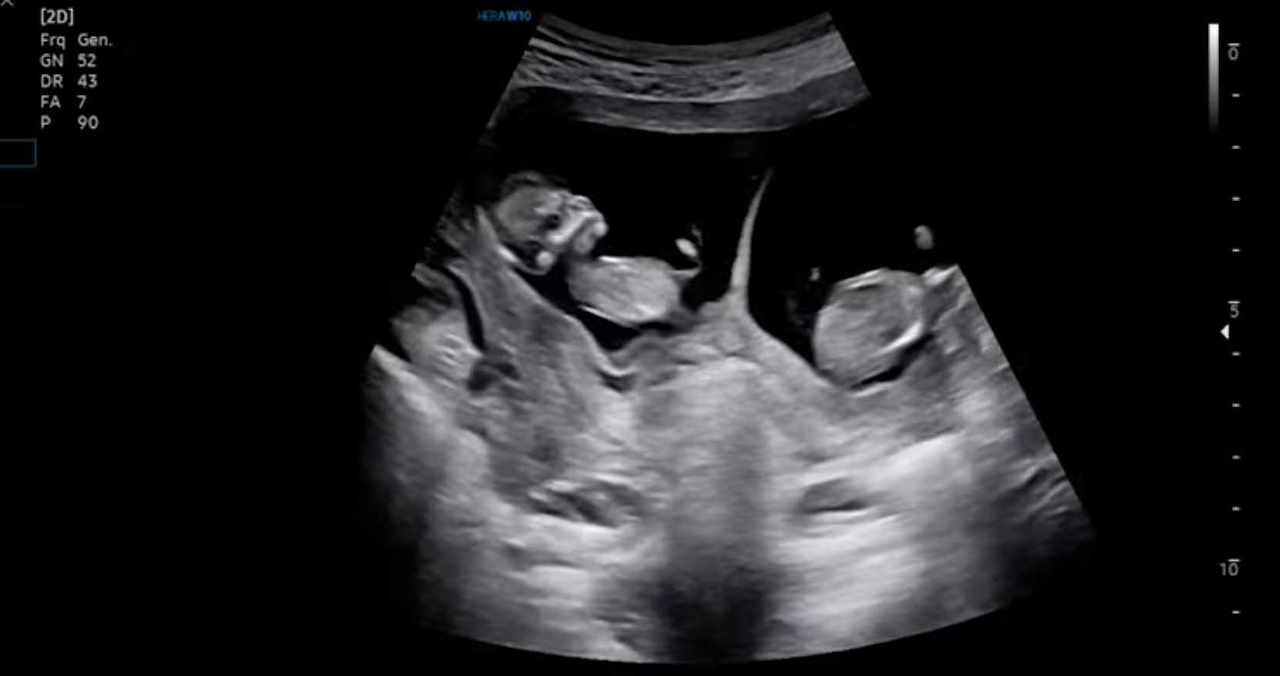

뱃속의 아기가 한명이 아니라 두명인 것을 알았을 때, 나와 남편은 생각보다 차분했다. 앞으로 일어날 일에 대한 감조차 오지 않았기 때문이다.